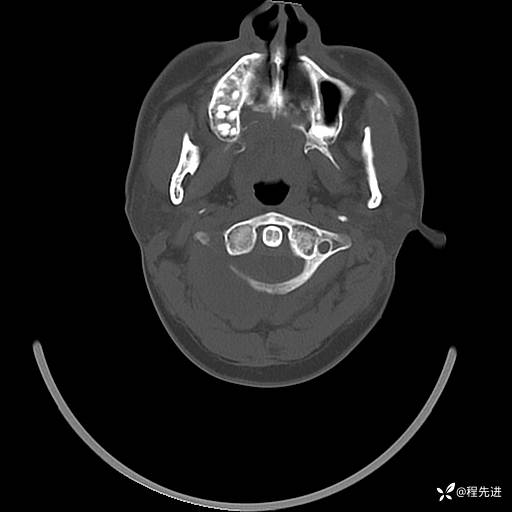

CT平扫+增强: